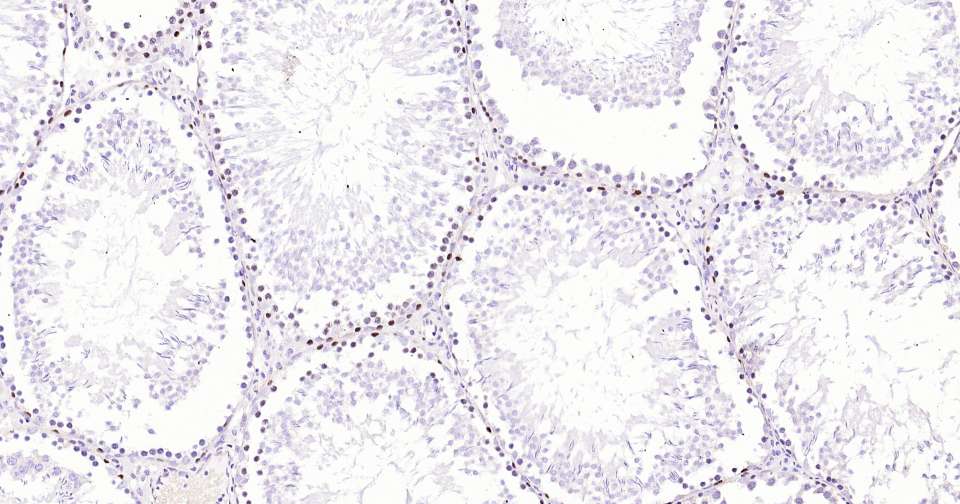

Immunohistochemical analysis of paraffin embedded rat testis tissue slide using IHC0337R (Rat Dnmt3a Kit).